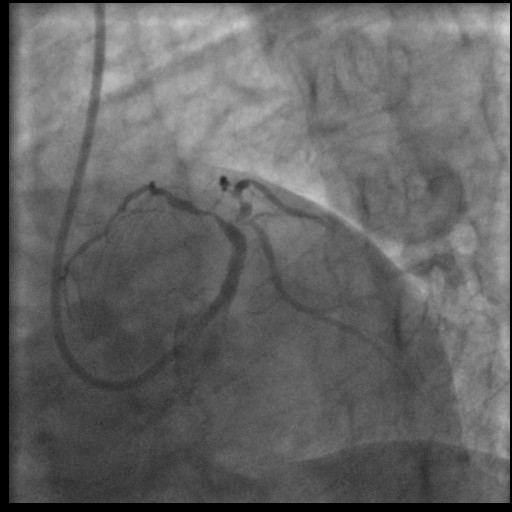

PPCI was done with GC XB 3,5/6F, followed by wiring the LAD using GW RNS hypercoat and double wired LCX using GW Sion Blue. Thrombosuction couldn¡¯t pass the tight lesion in LM, so we removed the Sion Blue, and continued the thombosuction from the LM to distal LAD. We successfully retrieved some thrombus, and we appreciate significant stenosis in the LM, with TIMI flow II. We did the balloon predilatation using SC balloon 2,5x15 mm (up to 14 atm), but the patient became unstable and VT. CPR and defib 200 J was done. After stabilisation, we evaluate that the flow was greatly reduced, back to TIMI flow 0. Thus we decided that we have to restored the flow as soon as possible, we did stenting with DES 3,5x16 mm (up to 14 atm). TIMI flow III was achieved, despite there is still lesion in LAD and the LCX. Due to limited resources and patient was stabilized with good hemodynamic, we decided to stop the procedure. Patient stayed 2 days in ICU, and no further VT/VF episodes. Echocardiogram was done, EF was 43% (biplane), and we still appreciated the wall motion abnormality in anterior segment. He was discharged in 5th days. Without chest pain and stable with good hemodynamic. ECG showed complete ST-segment resolution without Q-wave. He was then referred to a bigger hospital with better resources to achieved a complete revascularization.

after thrombosuction.avi

TIMI Flow reduced again.avi

post PPCI.avi